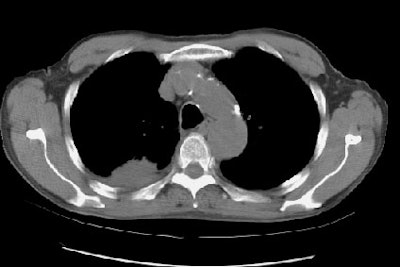

Example of brain metastases: This patient with non-small-cell lung cancer presented with left vocal cord paralysis. He did not have any neurological complaints. A central mass in the left lung was obstructing the left upper lobe bronchus (left image -- also note N2 subcarinal adenopathy). A head CT was requested by the patient's health care provider as part of the evaluation for his vocal cord paralysis and demonstrated multiple brain metastases, one of which is likely hemorrhagic (right fronto-parietal cortex).